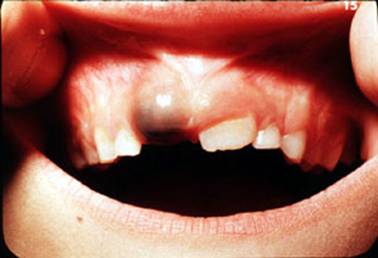

ICI posibil sa erupa :

Lingual cand NU mai exista ICI TEMPORAR. In timp datorita limbii isi va relua locul in arcul alveolar

Lingual cand INCA exista ICI TEMPORAR . Se va face extractia ICI TEMPORAR